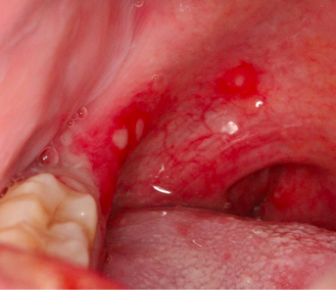

疱疹性咽峡炎

症状表现

疱疹急性发作,而且常常只集中在口腔内,手、脚等皮肤上没有皮疹。全年散发,夏季和初秋流行。

病变开始时为丘疹,在 24 小时内发生囊泡。囊泡通常直径为 1~2 毫米,并被红斑乳晕所包围。大约 24 小时后,囊泡破裂,形成直径 3~4 毫米浅黄或灰白色溃疡,边缘发红。疱疹数目比较多,分布在上颚、颊粘膜、唇粘膜等口腔内部粘膜,多于上颚后壁。

也就是说口腔疱疹是一个变化过程,早期是红点,然后发展为小水泡,最后破溃后形成小溃疡。可以伴随发热。

图片来源:[1]

如何处理

• 多在 1 周左右自愈,不需要特殊治疗。

• 宝宝因疼痛都不愿意吃东西,可以以牛奶、豆浆、米汤等流质食物为主,少食多餐;为了减少进食时嘴疼,避免过烫、过酸食物及刺激性食物。

• 体温超过 38.5℃ 时可给予退热药(如布洛芬或对乙酰氨基酚)。